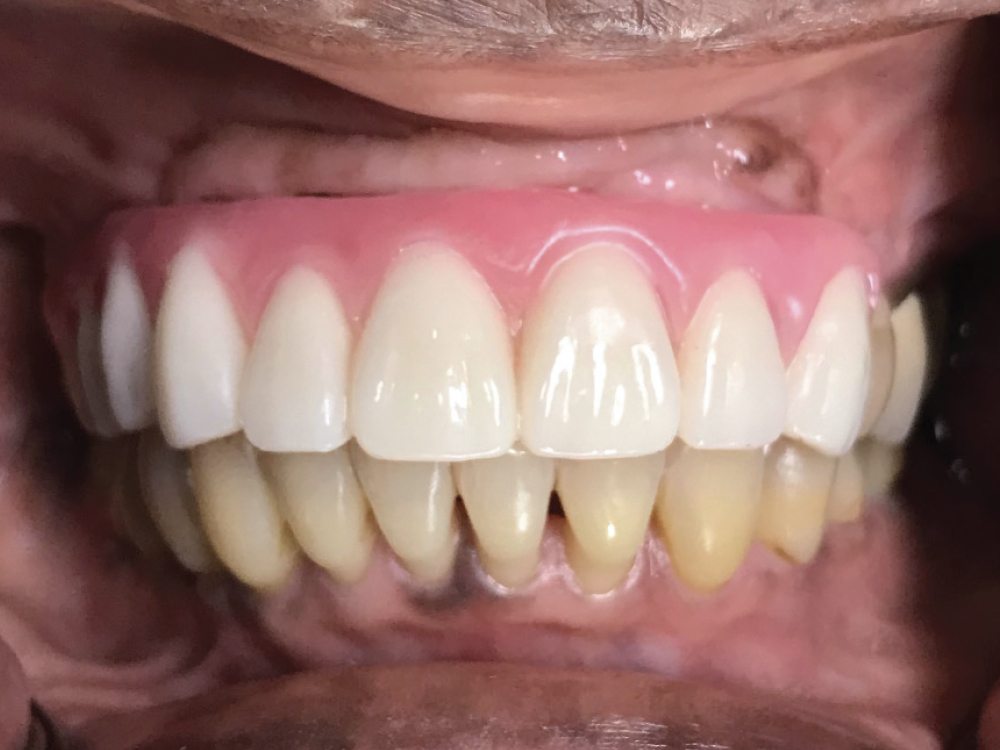

Figure 12: At the final delivery appointment, the BruxZir Esthetic Partial-Arch Implant Prosthesis was seated. We checked the occlusion, contacts, lateral excursions and phonetics, and everything was exactly as expected. The patient was extremely happy with the lifelike esthetics of the restoration and enjoys the ability to eat and smile with confidence.